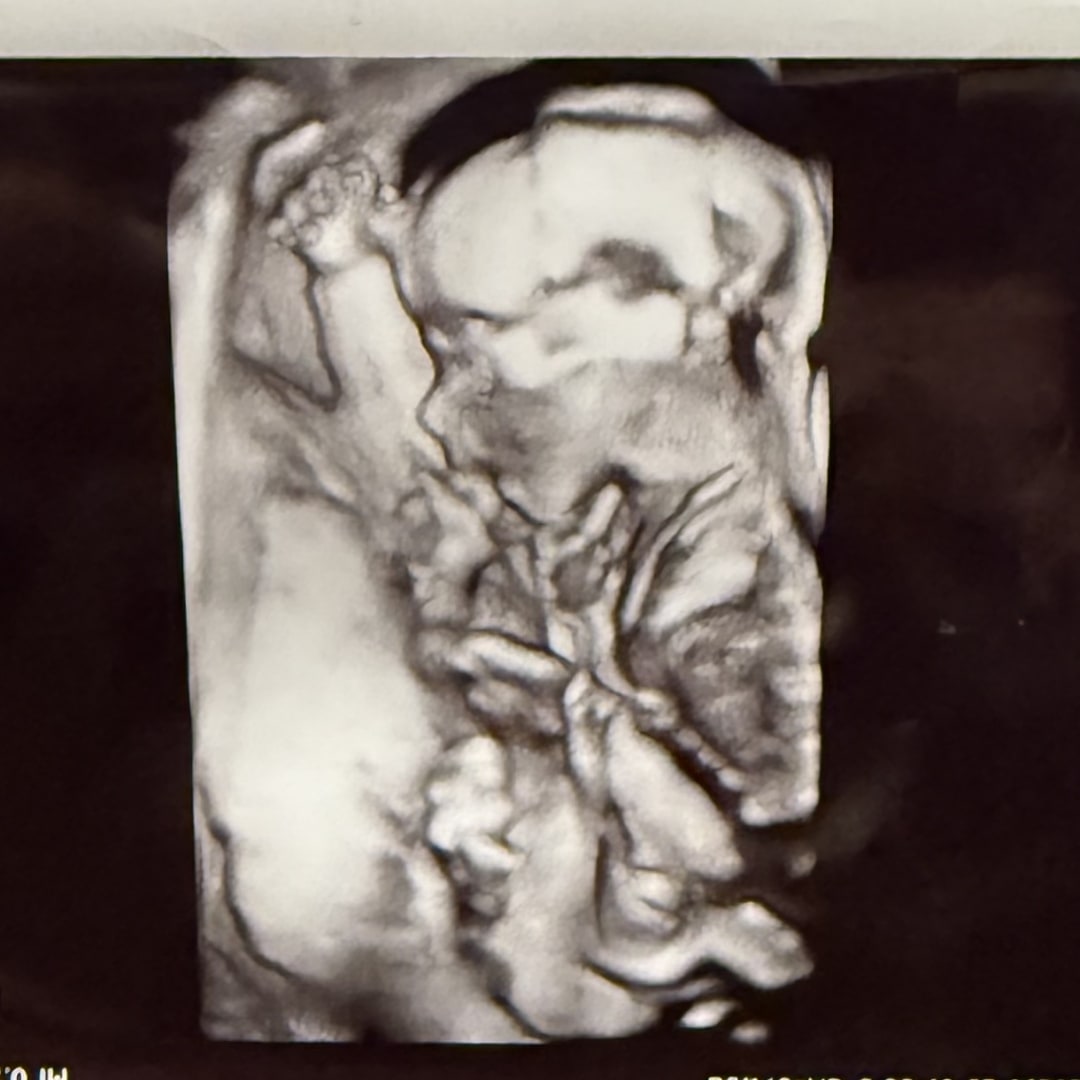

We are so excited for Baby girl! Thank you to anyone who is willing to help get us all settled and ready for her!